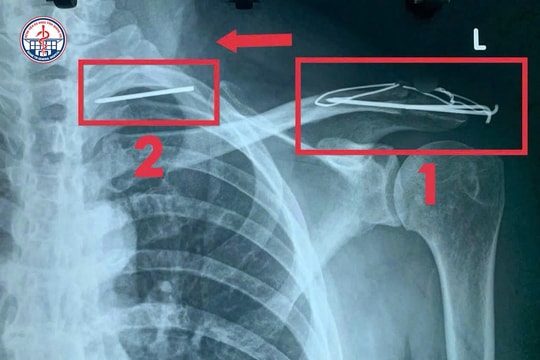

Hi hữu: Đinh phẫu thuật 'lang thang' trong lồng ngực bệnh nhân

05/09/2025 08:24

Bệnh viện Đa khoa tỉnh Quảng Trị vừa tiếp nhận và điều trị thành công một trường hợp dị vật kim loại di chuyển vào phổi rất hiếm gặp, tiềm ẩn nguy cơ đe dọa tính mạng.